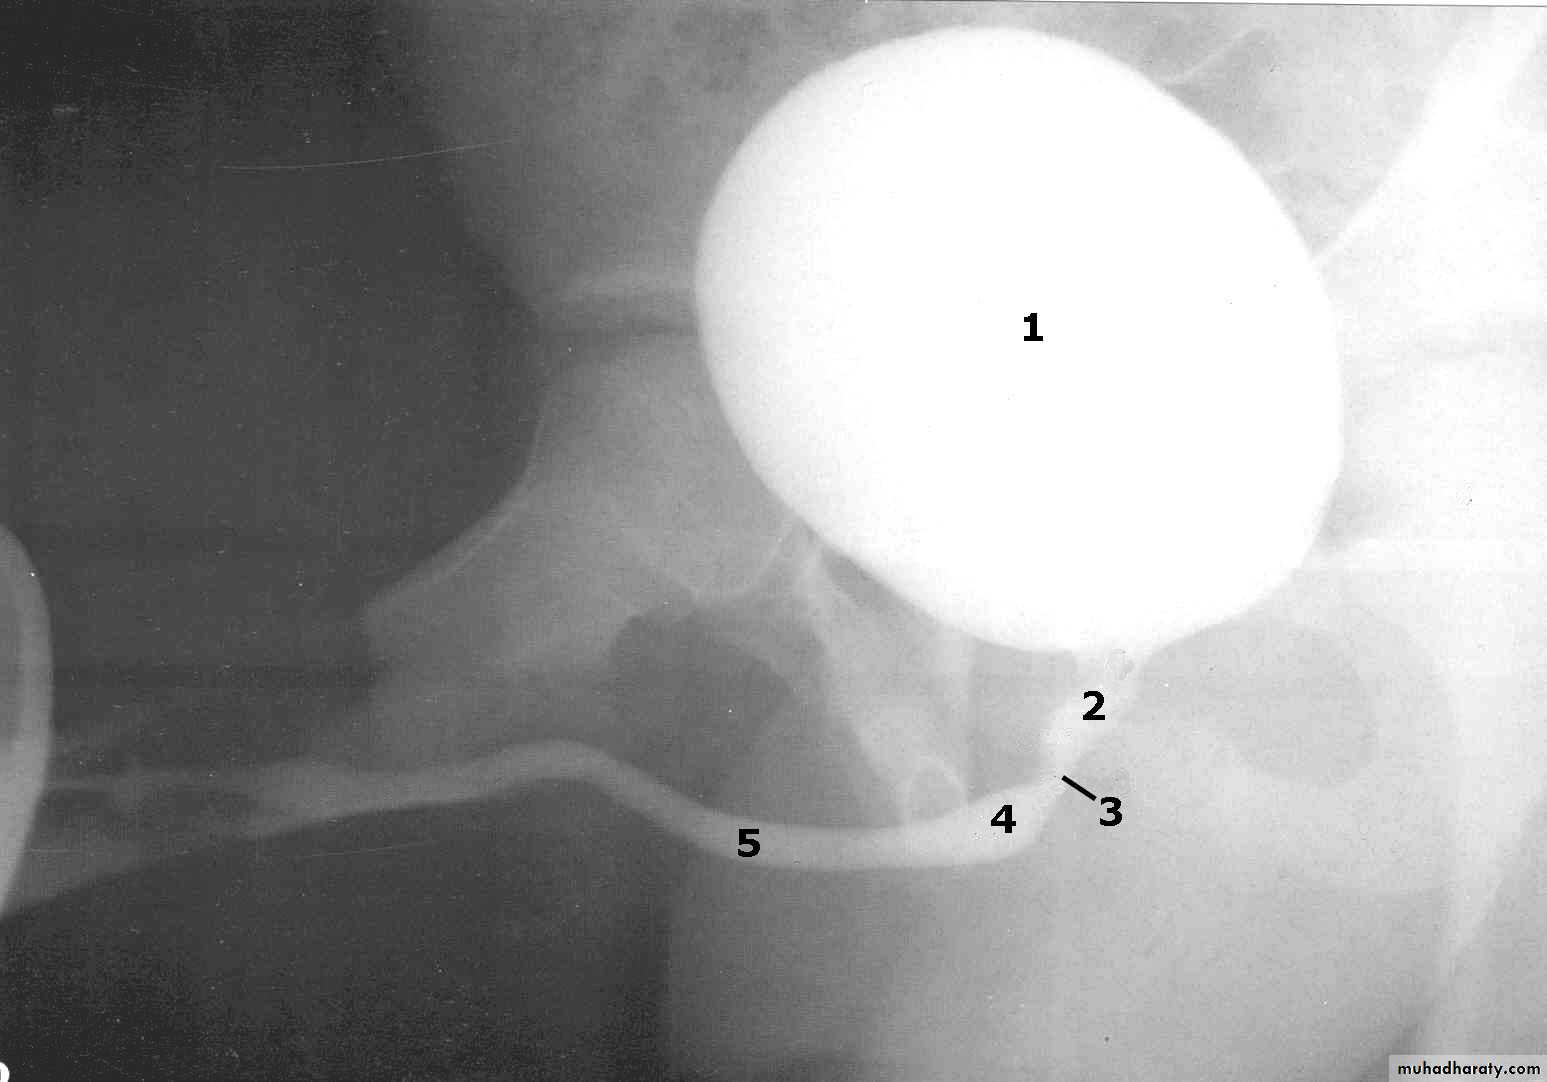

male &female reproductive tractsmammogram

genital tract and mammogram